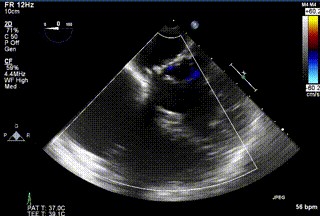

三例患者入院后,葛均波院士團隊周達新教授、潘文志教授、張源博士、陳莎莎博士及心超室的潘翠珍教授、李偉教授對患者的情況進行詳細評估和討論,最終決定為三例患者選擇LuX-Valve Plus40mm、50mm和50mm型號的瓣膜進行手術治療。手術后即刻拔除氣管插管,術后患者三尖瓣反流癥狀得到顯著改善,復查心超結果顯示人工三尖瓣瓣膜支架固定穩(wěn)定,瓣葉關閉形態(tài)未見異常,未見明顯反流。